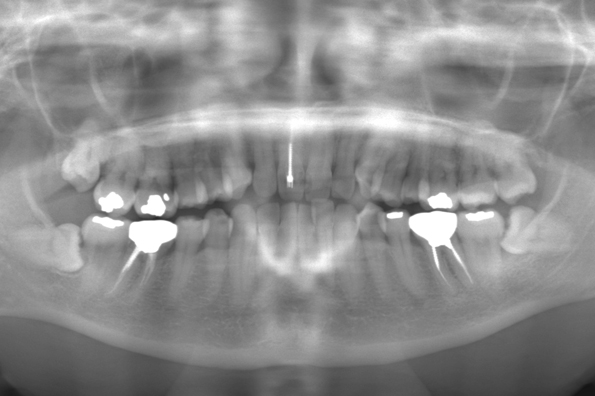

CASE 1

| 年齢・性別 | 30代・女性 |

| 主訴 | 左右に分けて親知らずを抜きたい、できれば痛くなく抜きたい |

| 親知らずのはえ方 | 完全に出ていてまっすぐはえている |

| 抜歯期間 | 15分 |

| 抜歯費用 | 約2,000円(保険内) |

| 抜歯内容 |

何度か虫歯になり痛みはないが早めに抜きたい。 完全に頭が出ているため歯ぐきを切ったり骨を削らずに抜歯しました。 根の形も単純なため抜歯自体は5分もかからず上下ともに終わりました。 術後痛みや腫れも出ていません。 抜歯後は感染をしやすいため必ず抗生物質を飲み切ってください。 |